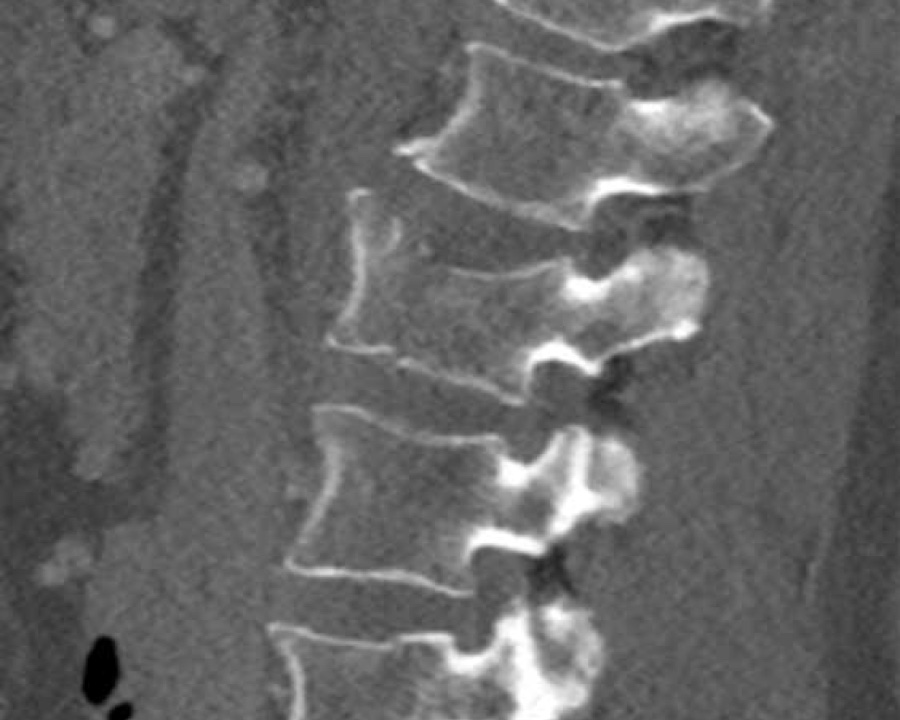

What is the type of the fracture of the vertebral body?

Findings:

- Fracture vertebral body with involvement of upper endplate (1 point), no posterior wall involvement

Conclusion

Injury type A1